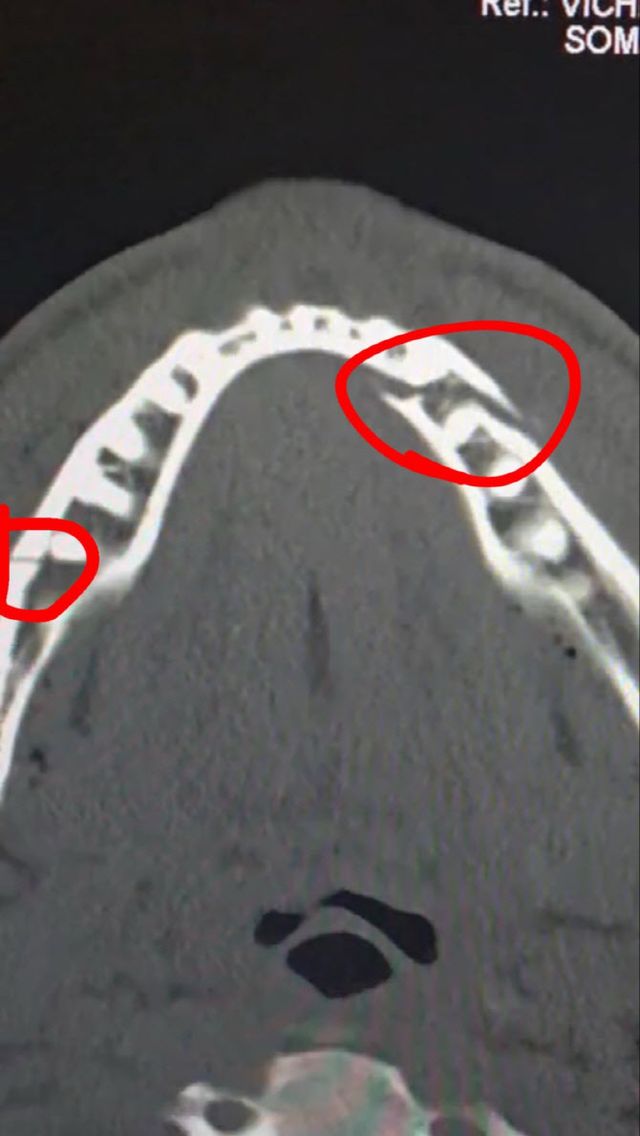

폴은 전 챔피언의 매서운 주먹맛을 제대로 느꼈다. 그는 “역대 최고 선수 중 한 명에게 제대로 한 방 먹었다”라며 “확실히 턱이 부러진 거 같다”고 말했다. 이후 병원을 향한 그는 사회관계망서비스(SNS)에 어금니 여러 개가 뒤로 밀린 엑스레이 사진을 올리기도 했다.

조슈아와 경기를 마친 폴은 잠시 숨을 고른 뒤 다시 링에 설 예정이다. 그는 “6년 동안 열심히 해왔으나 잠시 쉬어야겠다”며 “부러진 턱을 치료하고 제 체급 선수들과 싸우면서 세계 타이틀에 도전하겠다”고 말했다.